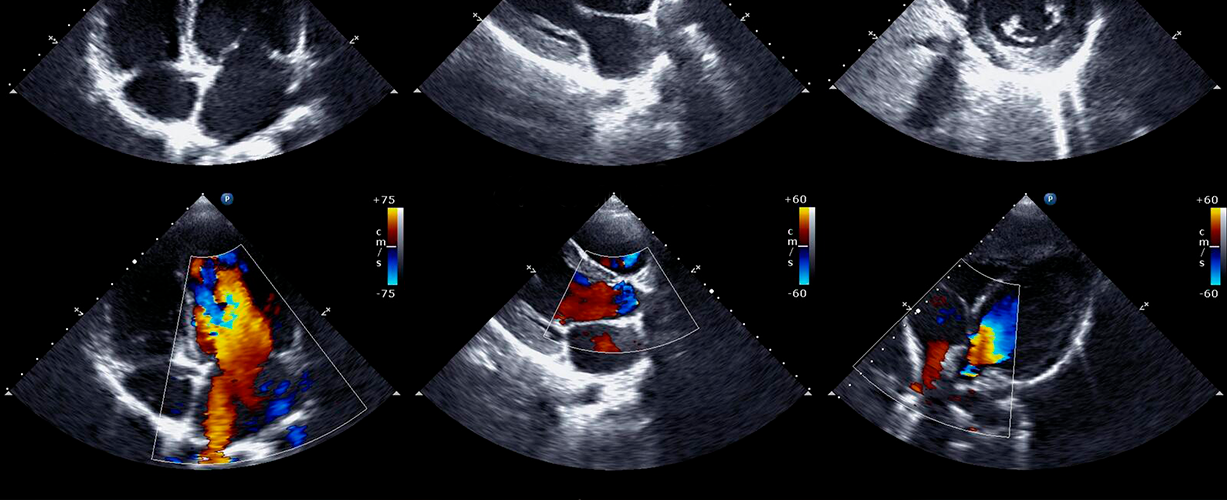

Лікар може аналізувати різні параметри, такі як розміри камер серця, товщина стінок, рухливість клапанів та інші характеристики. Додатково, кольорова доплерографія дозволяє візуалізувати напрямок та швидкість крові в судинах.

– Комп’ютер обробляє ехосигнали та формує детальне зображення серця та суміжних судин на екрані. - Доплерографія

– Під час процедури може використовуватися доплерографія для оцінки напрямку та швидкості крові в судинах. - Функціональне дослідження

– Лікар спеціалізованого профілю, зазвичай кардіолог чи сонографер, аналізує отримані зображення для оцінки структур серця. Він визначає розміри камер, товщину стінок, рухливість клапанів та інші анатомічні параметри. - Доплерографічний аналіз

– Якщо була застосована доплерографія, лікар аналізує напрямок та швидкість крові в судинах, що дозволяє визначити стан кровообігу та ідентифікувати можливі порушення. - Порівняння з нормою